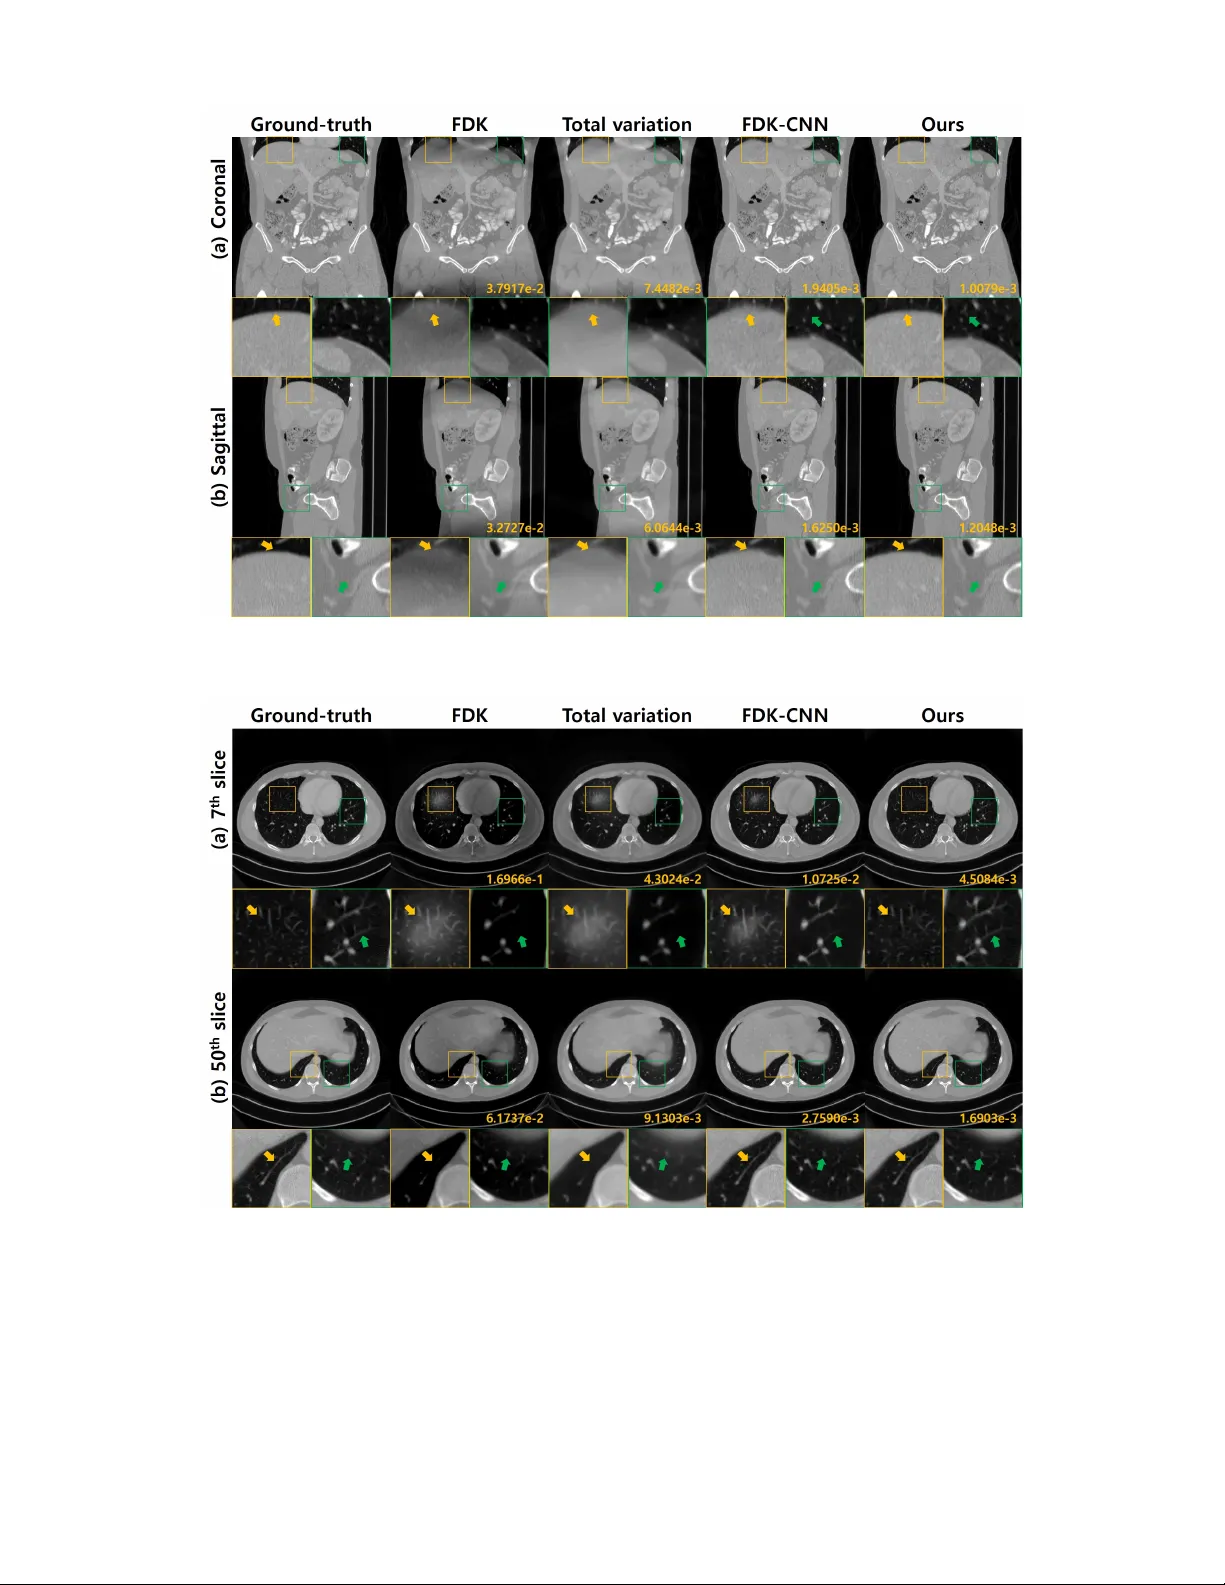

본 논문은 원뿔빔 CT의 원형 궤도에서 발생하는 콘빔 아티팩트를, 미분 역투영(DBP) 도메인에 설계된 인코더‑디코더 CNN을 이용해 데이터‑드리븐 방식으로 복원한다. DBP 데이터를 코롤라 및 시상면으로 분리하고, 각 면에서 Hilbert 변환에 기반한 비선형 디컨볼루션을 학습한 뒤, 스펙트럼 블렌딩으로 두 결과를 결합해 누락된 주파수 영역을 보완한다. 실험 결과, 기존 모델 기반 반복 재구성보다 연산량은 크게 줄이면서도 재구성 품질이 우수함을 확인하였다.

실험에서는 시뮬레이션 데이터와 실제 측정 데이터를 모두 사용했으며, 훈련은 노이즈가 없는 시뮬레이션으로 진행했음에도 불구하고, 노이즈가 섞인 실제 데이터에 대해 뛰어난 일반화 성능을 보였다. 또한, 동일한 네트워크를 다양한 콘빔 각도에 적용했을 때 재학습 없이도 안정적인 복원을 수행한다는 점에서, 학습된 필터가 물리적 기하학적 변동성을 내재적으로 학습했음을 시사한다. 전체 파이프라인은 전통적인 FDK + 반복 재구성 대비 10배 이상 빠른 실행 시간을 기록했으며, PSNR·SSIM 등 정량적 지표에서도 현저히 우수한 결과를 얻었다.